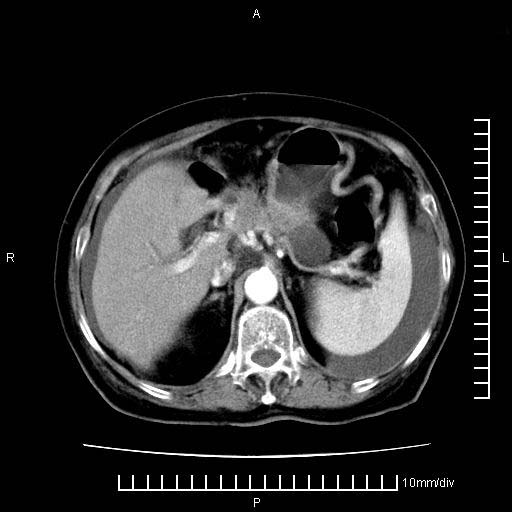

标题: CT28280:腹部增强:女性,80岁

上腹疼痛月余,外院核磁诊断胰腺癌。现临床示右下腹可明显触及包块,可片子上怎么没有看到?

1。胰腺ca伴腹膜腔转移

2。肝左叶低密度灶,考虑转移可能

支持胰腺癌肝内转移,腹水改变。

1、考虑胰腺癌伴腹膜腔转移,胸腹水。

2、肝脏转移可能。

考虑胰腺ca伴腹膜腔转移、肝左叶转移、右肾积水。右胸腔积液。

考虑胰腺ca伴腹膜腔转移、肝左叶转移、右肾积水。右胸腔积液。支持